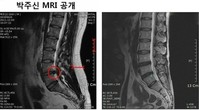

강용석, 으름장 놓다!..“박원순, 다른 MRI 공개할 경우 ‘입수경로’ 밝히겠다”

박원순, 아들 MRI 공개 선언..일 더 키웠다!

박원순 서울시장의 ‘아들 MRI(자기공명영상) 공개 선언’이 일을 더욱 키웠다.이번엔 회원 6천명 규모의 전국의사총연합(전의총)이 ‘박주신 MRI’ 정밀분석에 나섰다. ‘박주신 MRI 필름’으로 알려진 영상 속 주인공은 실제 박원순 시장의 아들일 가능성이 거의 없다는